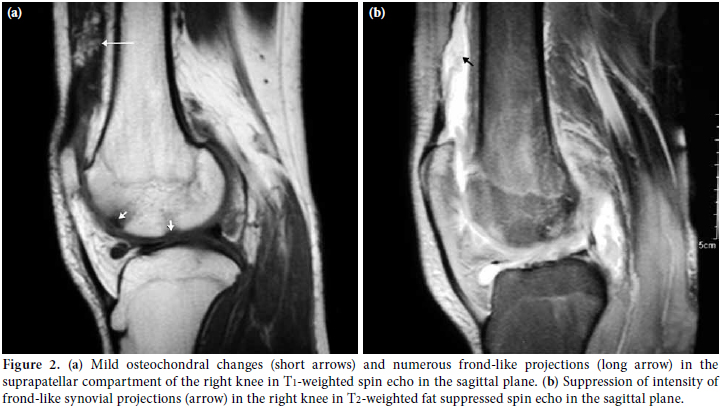

Magnetic resonance imaging revealed a large effusion and numerous frond-like projections which were prominent in the suprapatellar compartment of right knee. The intensity of these frond-like synovial projections, which were suppressed in fatsaturated sequences, was similar to the intensity of fat (Figures 2a, b). An effusion and a mass-like lesion were also detected in the popliteal bursa of the right knee. (Figures 3a, b) In addition, mild osteochondral changes occurred in both knees which were more pronouced on the right side (Figure 2a). Suprapatellar effusion was also detected in the left knee. No meniscal or ligament pathology was detected in either knee.

Because of its histological nature, MR imaging findings of LA are accepted as typical and help us for a confident preoperative diagnosis. Magnetic resonance imaging is highly accurate for the identification and characterization of LA and is the best imaging modality and the cornerstone of the preoperative diagnosis.[13-15] Villous synovial proliferations with a signal intensity similar to that of fat in all sequences, mass-like subsynovial deposits, large effusions, potential demonstration of associated chemical shift artifact at the interlace of the synovial lesion and the effusion, and no evidence of hemosiderin deposition are included in the MRI results identifying LA.[1,3,5,7] These typical results allow for a confident preoperative diagnosis and can exclude other possible clinical and radiological mimickers,, such as synovial osteochondromatosis, pigmented villonodular synovitis, synovial hemangioma, and synovial lipoma.[14,15] In our cases, there was prominent suprapatellar effusion and synovial hypertrophy. In the fat-suppressed MRI, the fatty nature of the focal areas was more clearly demonstrated. Pigmented villonodular synovitis (PVNS), synovial chondromatosis, RA, intraarticular lipoma, and synovial hemangiomas should be considered in the differential diagnosis of LA as they usually present with painless synovial thickening and effusion. In PVNS, there are focal areas of hemosiderin deposits characterized by significantly low signal intensity in both T1- and T2-weighted images. There is also contrast enhancement in PVNS. Synovial chondromatosis is defined by multiple cartilaginous nodules. These nodules have intermediate-to-high signal intensity in T2-weighted images and low-tointermediate signal intensity in T1-weighted images. Synovial hemangiomas appear as either intraarticular or extraarticular lesions of intermediate signal intensity on both T1- and T2-weighted images. There might be areas of focal low signal intensity. This suggests calcified phleboliths or fluid void in abnormal vessels. Synovial lipoma is another disorder that must be considered in differential diagnosis. In this disorder, MRI reveals a solitary, localized mass of adipose tissue without synovial changes. Chronic rheumatoid arthritis shows intermediate signal intensity on T1-weighted images and relatively decreased signal intensity on T2-weighted images within the synovium. This is associated with the formation of pannus. Lipoma arborescens is usually located in the suprapatellar recess. In contrast, PVNS, synovial hemangiomatosis, and lipoma are usually located in the infrapatellar fat pad of Hoffa.[1,10,17-19] According to the clinical and radiological/laboratory examinations and the MRI findings, we concluded that LA was the correct diagnosis in our cases. Although we referred our patients to orthopedics department for surgical synovectomy aiming not only to establish LA diagnosis conclusively, but also to treat the disease, family didn’t accept the surgical synovectomy. Therefore LA diagnosis could not be confirmed histologically in our patients, though MR imaging findings were highly suggestive of LA in both cases.